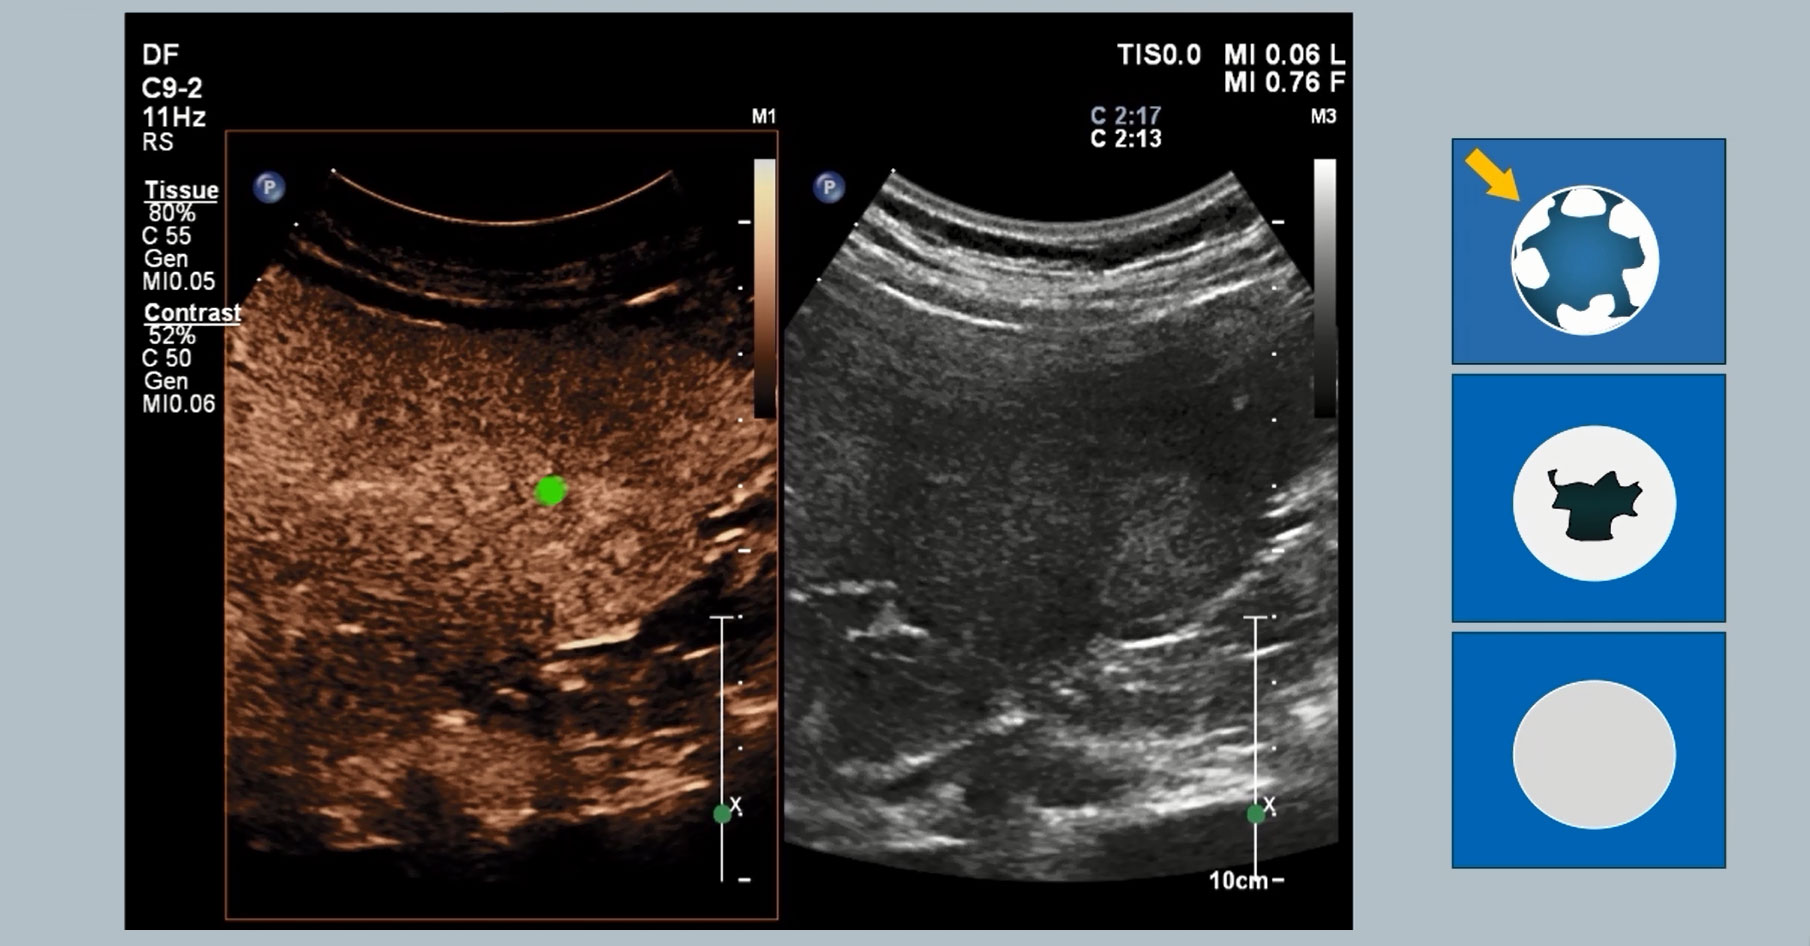

Philips Affiniti 70 with PureWave technology

Ben Stenberg, PhD, discusses his experience with the Affiniti 70 in the busy radiology department of Freeman Hospital NHS in Newcastle upon Tyne, UK.